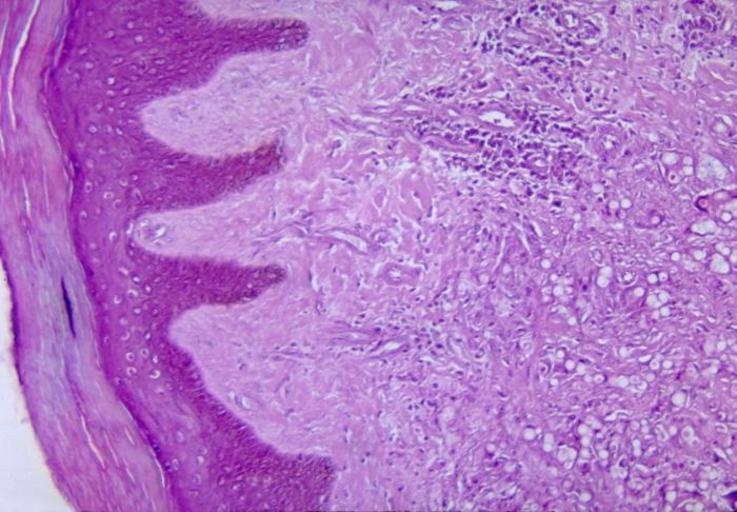

MAKE A MEME View Large Image Lobomycosis.jpg Histopathological changes in lobomycosis skin This chronic fungal infection is caused by the fungus Loboa loboi and is characterized by keloidal nodular lesions occurring on the face ears or extremities This disease is ...

Keywords: Lobomycosis.jpg Histopathological changes in lobomycosis skin This chronic fungal infection is caused by the fungus Loboa loboi and is characterized by keloidal nodular lesions occurring on the face ears or extremities This disease is usually found in humans and bottle-nosed dolphins Source CDC PHIL image database public domain PD-USGov original upload log page en wikipedia Lobomycosis jpg 2006-01-22 18 42 Rsabbatini 700×486× 71962 bytes <nowiki>Histopathological changes in lobomycosis Source CDC PHIL image database public domain CDC </nowiki> Bright-field microscopic images Lobomycosis Histopathology